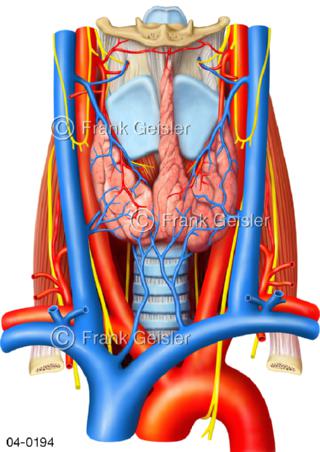

Bildergalerie Topografie Organe

Bilder zur topografischen Anatomie, die Lage der Organe und die Strukturen nach ihren räumlichen Lagebeziehungen zueinander, Übersicht der inneren Organe im Kopf und im Rumpf, Topografie der Organe im Brustraum (Thorax) und im Bauchraum (Abdomen)